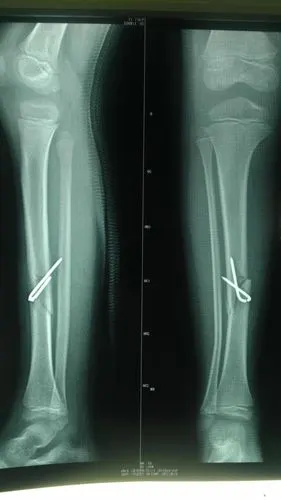

仔细看腓骨,有青枝骨折

胫腓骨骨折a0.b1

书上称胫骨骨折而腓骨青枝骨折或无明显的骨折线但有异常弯曲者称之为